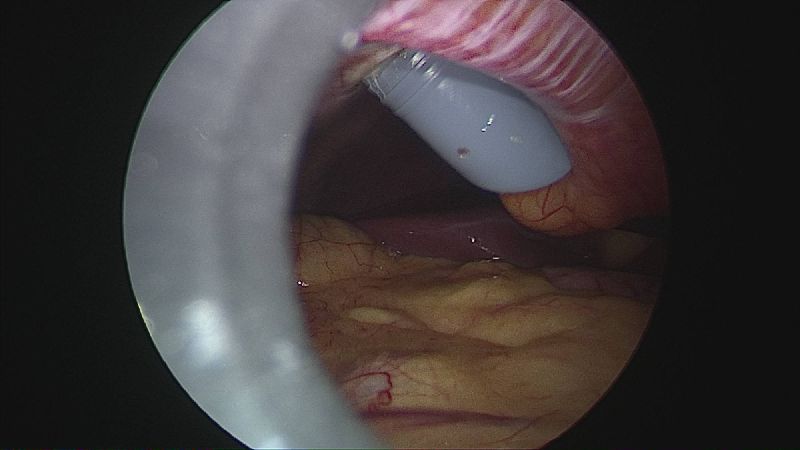

Operația ”de micșorare a stomacului” se realizează miniminvaziv (laparoscopic) și constă în îndepărtarea marii curburi gastrice cu păstrarea antrului gastric și a micii curburi sub forma unui tub calibrat pe o sondă.

Tehnica aduce beneficiile chirurgiei laparoscopice, durere redusă, externare în primele 48 ore de la intervenție. Avantajul său constă în confortul oferit pacientului care prezintă senzația de sațietate rapid prin umplerea unui stomac de doar 100 ml, reducerea senzației de foame prin suprimarea secreției de grelina. De asemenea, nu modifică traseul alimentelor, nu exclude segmente digestive din circuit și pierderea excesului ponderal poate ajunge până la 100%.